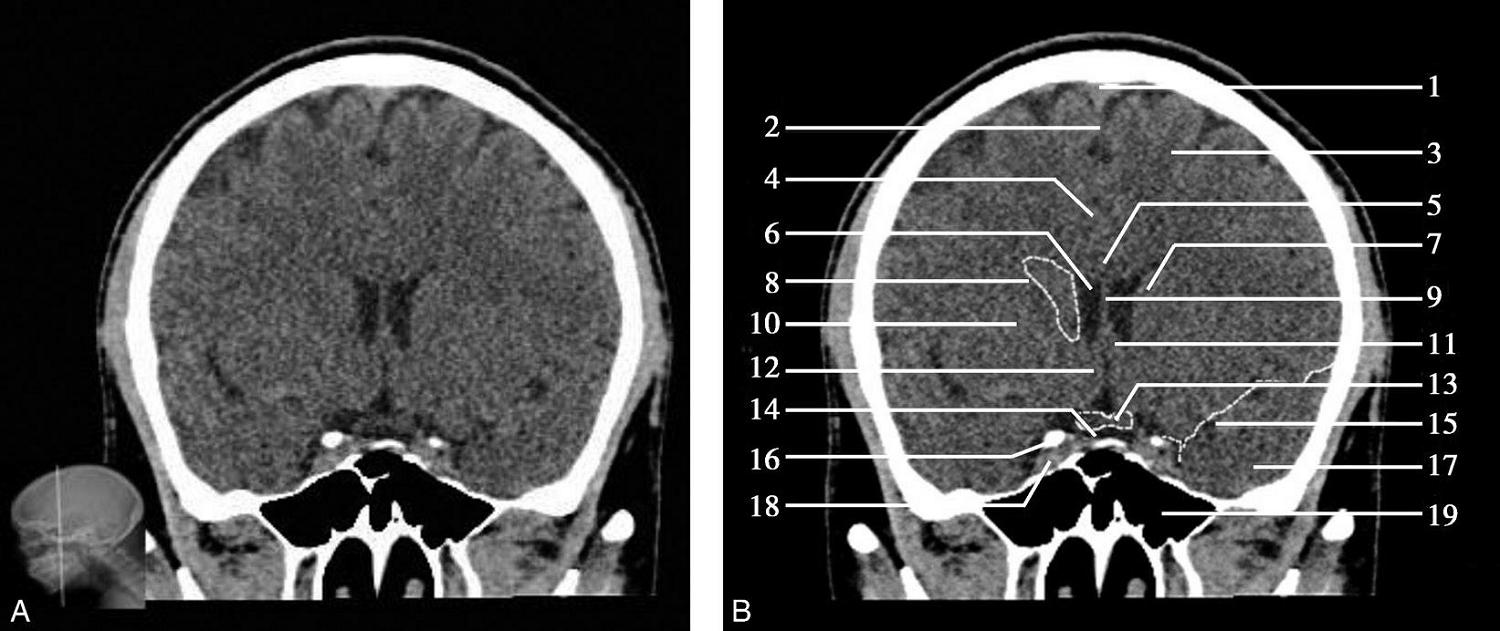

重要结构:视交叉、尾状核头、额叶、颞叶、外侧裂池(图1-2-52、图1-2-53)。

图1-2-52 视交叉层面

A.冠状面;B.冠状面标注

1.上矢状窦;2.大脑镰;3.额叶;4.扣带回;5.胼胝体体部;6.侧脑室前角;7.尾状核头部;8.内囊前肢;9.透明隔;10.豆状核;11.隔核;12.伏隔核;13.视交叉;14.鞍上池;15.外侧裂池;16.前床突;17.颞叶;18.海绵窦;19.蝶窦

图1-2-53 视交叉层面(骨窗)

1.矢状缝;2.顶骨;3.顶颞缝;4.前床突;5.颞骨;6.蝶鳞缝;7.蝶窦;8.颧弓;9.翼突内侧板;10.翼突外侧板

此层面正中线上部有大脑纵裂池及其内的大脑镰,大脑镰的上端与上矢状窦相连,下端毗邻胼胝体体部,胼胝体纤维连接双侧额叶。双侧额叶的外侧面,自上而下有额上回、额中回及额下回。胼胝体体部上方大脑镰的两侧有扣带回及扣带沟。胼胝体体部下方正中是透明隔,其两侧近似三角形为侧脑室前角,侧脑室前角顶壁为胼胝体,内侧壁上部为透明隔,底壁由隔核与伏隔核组成,外侧壁为尾状核头部。尾状核头外侧依次为内囊前肢、豆状核、外囊及屏状核。内囊位于尾状核头的外下方,是大脑皮质与皮质下中枢间的上下行纤维组成的投射纤维的主要通路。豆状核位于内囊的外下方,分为内侧的苍白球及外侧的壳核。胼胝体嘴部下方自上而下依次为大脑纵裂池、视交叉、鞍上池。视交叉两侧外下方为前床突的骨性断面,前床突内下方为海绵窦,其内可见颈内动脉断面,前床突外侧为两侧颞叶,两侧额叶与颞叶借外侧裂池分隔,额叶位于外侧裂池上方,颞叶位于外侧裂池下方。海绵窦下方中线区为蝶窦,蝶窦下方中部为鼻腔,鼻腔两侧为颞下窝。